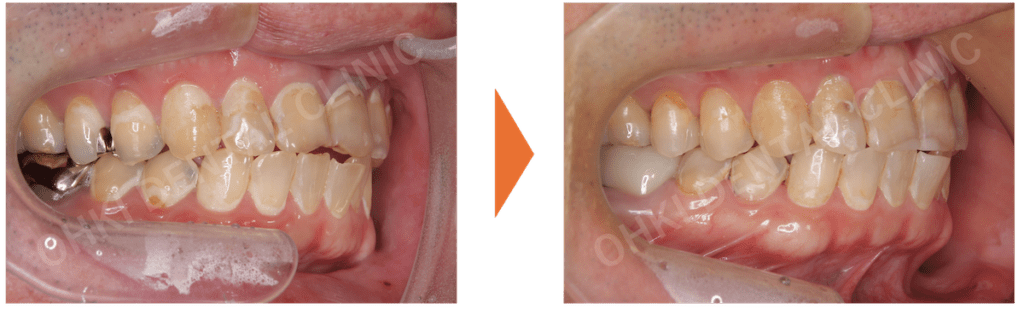

・主訴である右下7番は、コアごと脱離しており、歯根破折を認めました。

・パノラマレントゲン写真では、左下6番にも歯折と周辺の骨吸収が認められました。

・全体的にカリエス(虫歯)が多く、非常にカリエスリスクが高い状態でした。

Before / After の比較:

治療前と比べて、上の前歯の正中離開(スキッパ)は改善されました。

- インプラントを埋入したことにより、噛む機能が回復したことが大きな結果です。

- 噛み合わせの柱が再建されたことで、今後、残存している歯の破折リスクや負担が軽減されました。